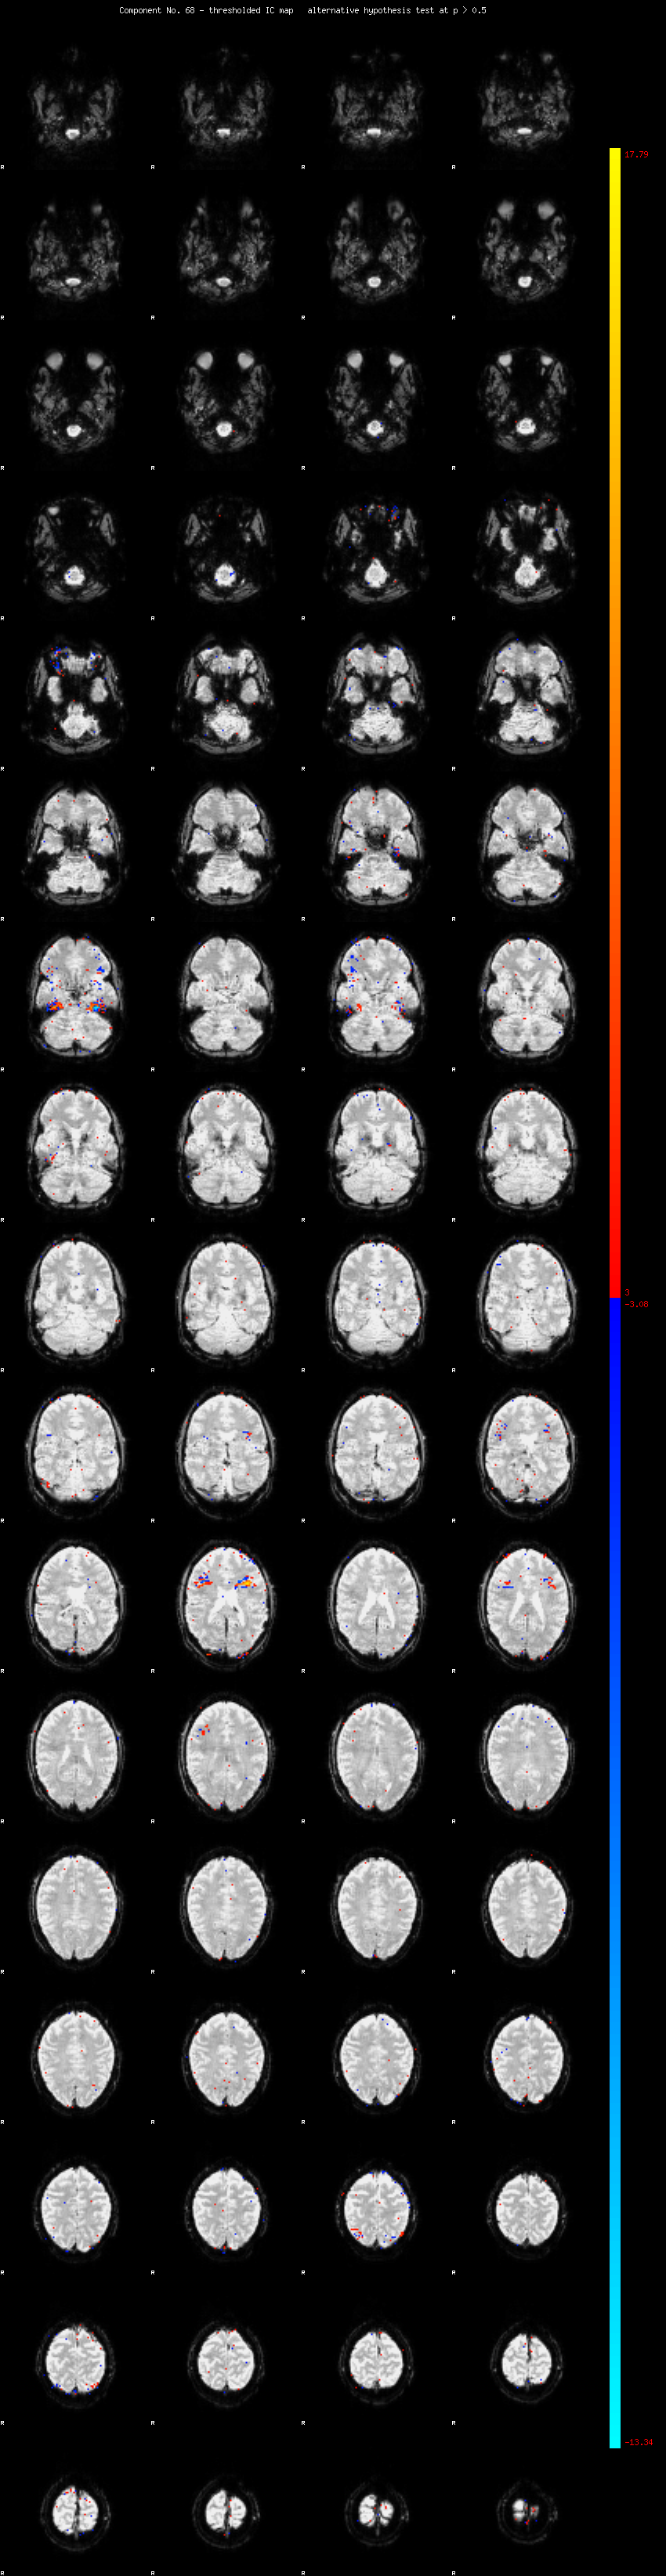

MELODIC Component 68

0.78 % of explained variance;     0.52 % of total variance

MMfit